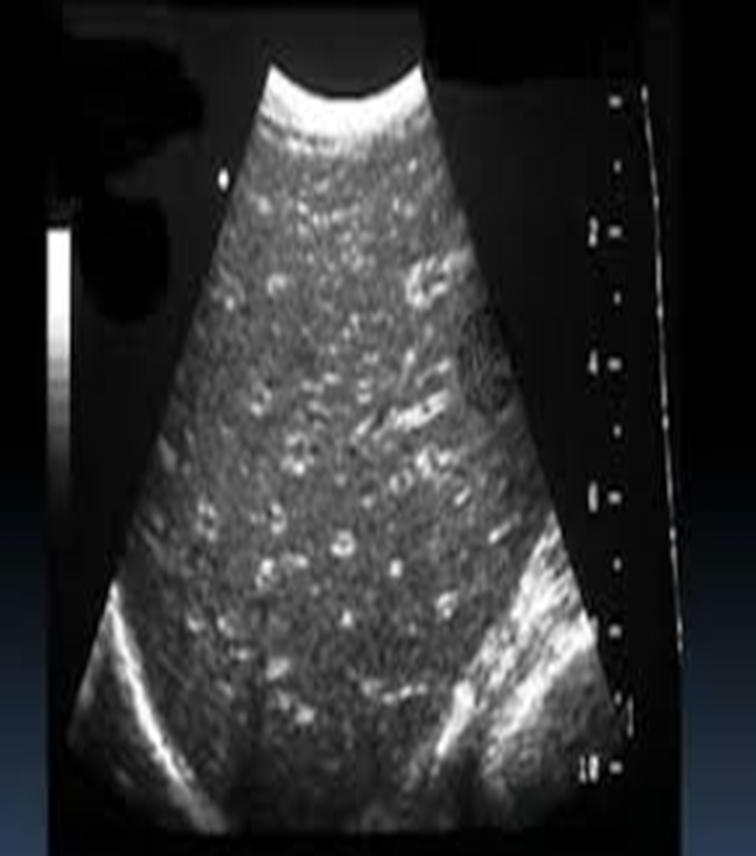

acute hepatitis sonographic appearance

hypoechoic

periportal cuffing (starry sky)

starry sky occurs due to

acute hepatitis

starry sky

likely due to acute hepatitis

acute hepatitis with starry sky

starry sky aka

periportal cuffing